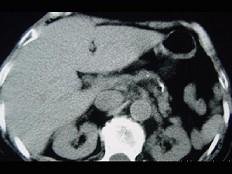

问题 女,54岁,中上腹痛,体重减轻,消化不良,脂肪痢、便量多、泡沫状。影像检查如下图,最佳诊断是 ( )

选项 A.急性胰腺炎 B.慢性胰腺炎 C.胰腺癌 D.急性出血坏死性胰腺炎 E.胰岛素瘤

答案 B